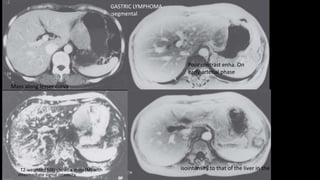

, T2-weighted MRI shows a mass (M) with

intermediate signal intensity.

Mass along lesser curva.

Poor contrast enha. On

early arterial phase

isointensity to that of the liver in the delayed phase (D).

GASTRIC LYMPHOMA

:segmental